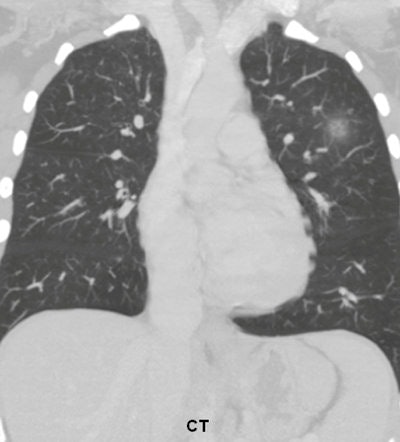

A 36-year-old woman with focal pneumonia. Top: Portable chest radiograph shows focal airspace opacity in left upper lobe and a very small nodule in right upper lobe (arrows). Above: Bone suppression image shows these airspace opacities more clearly. Below: Coronal reconstruction from CT scan performed five days later. The right opacity had resolved and the left opacity had decreased on the follow-up CT. All images courtesy of Dr. Feng Li.